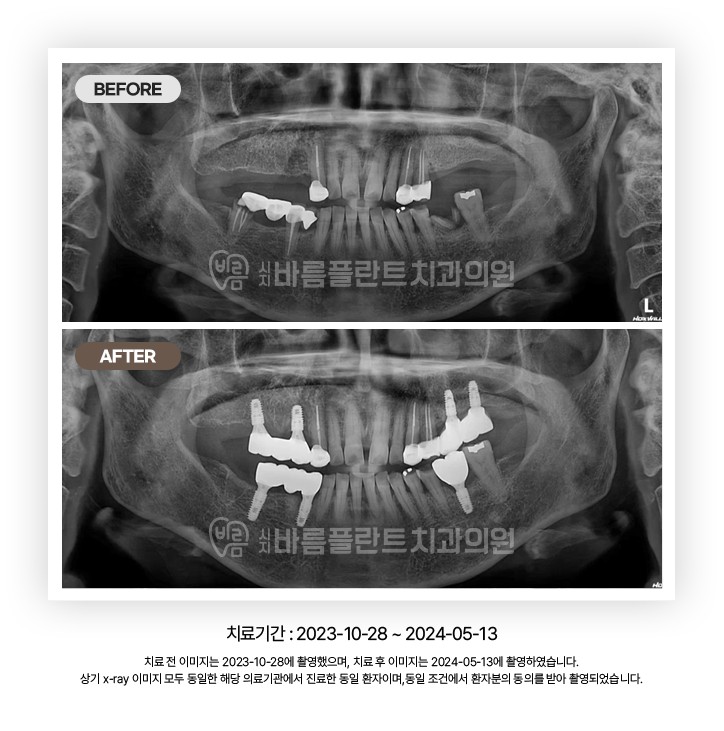

임플란트 CASE